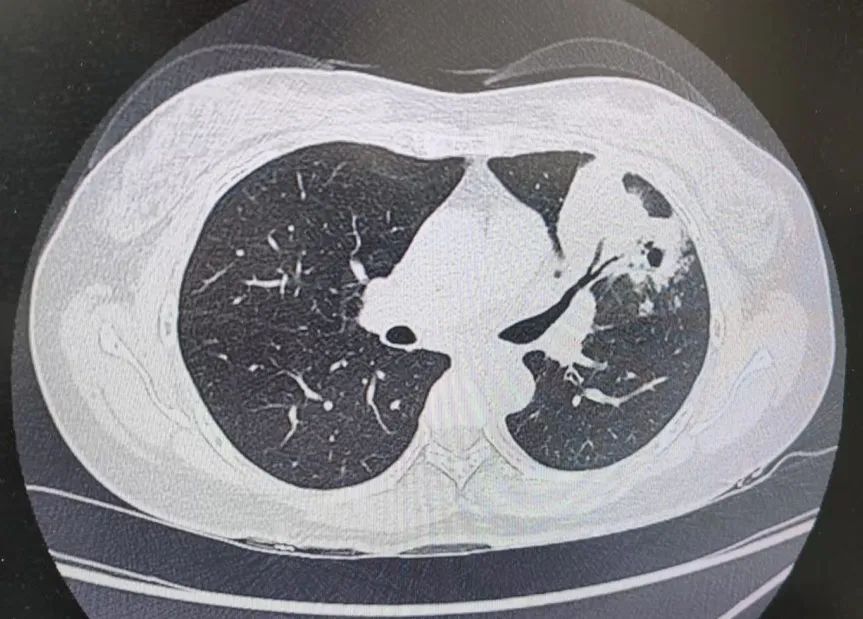

患者肺部CT影像

“一般來(lái)說(shuō),肺炎經(jīng)過(guò)一周的抗感染治療,病灶會(huì)有所吸收。但陳女士的肺部陰影紋絲不動(dòng),這種情況必須提高警惕。”宋剛主任團(tuán)隊(duì)立即啟動(dòng)了更深入的“三部精準(zhǔn)診斷”程序:

3、CT引導(dǎo)下穿刺活檢:病理診斷為左肺上葉腺癌。

肺炎型肺癌,因其影像學(xué)表現(xiàn)與普通肺炎極為相似,臨床上誤診率極高。然而確診僅是第一步。宋剛主任當(dāng)天即召集腫瘤科、病理科、影像科等多學(xué)科專家會(huì)診,為陳女士制定個(gè)體化治療方案。